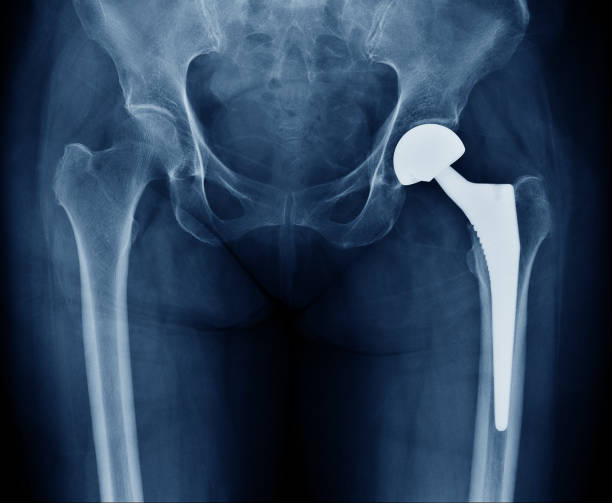

"Achieve Optimal Joint Health: Dr. S.S. Soni's Exp...

hip knee ankle elbow Guide Jaipur freedom shoulder Dr. Soni commitment active life unique needs Dr. S.S. Soni wrist conditions Enhanced Mobility joint replacements Expert Arthroscopy latest advancements advanced arthroscopy Optimal Joint Health patient-centric care wrist replacement surgery joint replacement surgery Joint Replacement Services arthroscopic interventions personalized treatment plans dedicated orthopedic surgeon Arthroscopic Joint Treatments unparalleled orthopedic expertise